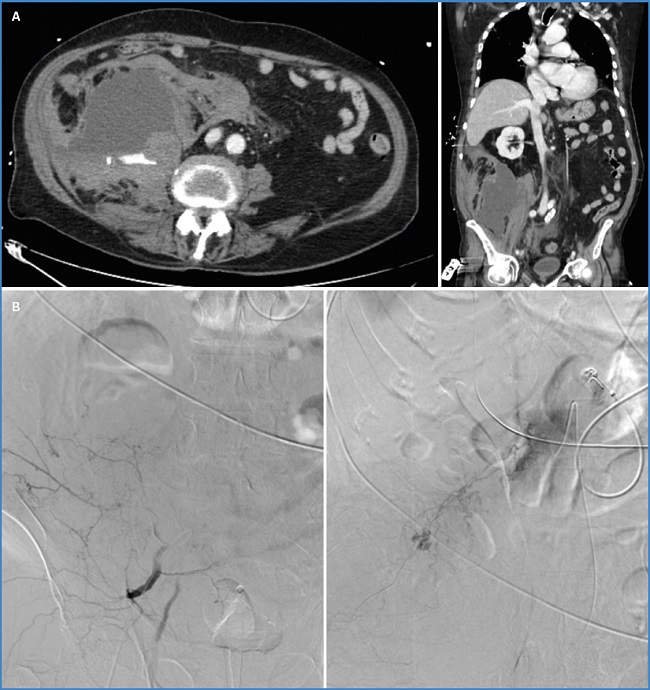

La sospecha de un HRE debería establecerse con base en la clínica y requiere confirmación diagnóstica de forma urgente mediante angio-TC con contraste intravenoso (Fig. 4A). En el caso de pacientes jóvenes o mujeres embarazadas, las pruebas de imagen podrían basarse en la ecografía o la resonancia magnética (22). Las determinaciones analíticas deberían incluir el control seriado de los niveles séricos de hemoglobina y hematocrito, aunque debe tenerse en cuenta que estos pueden ser normales al inicio del sangrado. De hecho, solo un 37,5 % de los pacientes valorados en este estudio presentaron alteración en los niveles séricos de hemoglobina al momento del diagnóstico.

Figura 4. A. TAC abdomino-pélvico. Hematoma adyacente al músculo psoas ilíaco derecho a la altura de L3-L4 de aproximadamente 15 × 12,8 × 17 cm con focos de extravasación de contraste en fase arterial. Hallazgos compatibles con sangrado activo. B. Arteriografía y embolización de varios puntos de sangrado activo dependientes de arterias lumbares, 12.ª arteria intercostal y arteria iliolumbar derecha.

En cuanto al manejo terapéutico de esta entidad, en la revisión bibliográfica realizada consta que en la mayoría de los casos se estableció un tratamiento inicialmente conservador del HRE con reposición de volumen mediante fluidoterapia intravenosa, transfusión de hemoderivados y corrección de las alteraciones de la coagulación. Por otra parte, en los pacientes con shock hipovolémico refractario a las terapias de resucitación inicial, presencia de hematoma retroperitoneal expansivo o signos de sangrado activo en la TC, estaría indicada la angioembolización como tratamiento de primera línea (Fig. 4B). Únicamente ante su fracaso, la presencia de patología quirúrgica concomitante o el acontecimiento de un de síndrome compartimental abdominal refractario al tratamiento médico (definido por una presión intraabdominal superior a 20 mmHg objetivada en 3 determinaciones estandarizadas, con disfunción secundaria de uno o varios órganos, por ejemplo, renal o restricción respiratoria) estaría indicada la intervención quirúrgica (22).